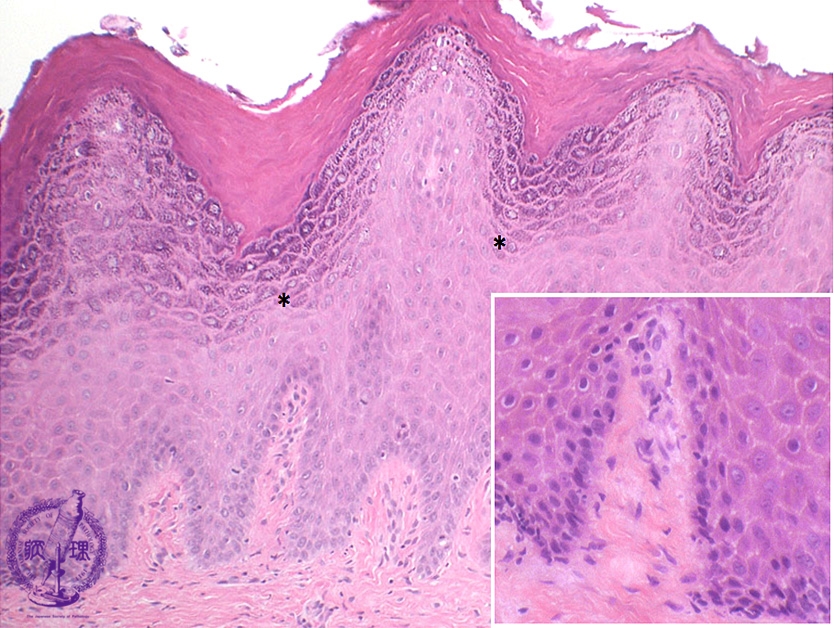

- (3)Oral mucosal diseases(★Leukoplakia:epithelial hyperkeratosis)

Microscopic finding (HE stain, intermediate and high-power view):The mucosa exhibits marked hyperkeratosis and hypergranulosis within the epidermis(*) but there is no cytological or architectural atypia.